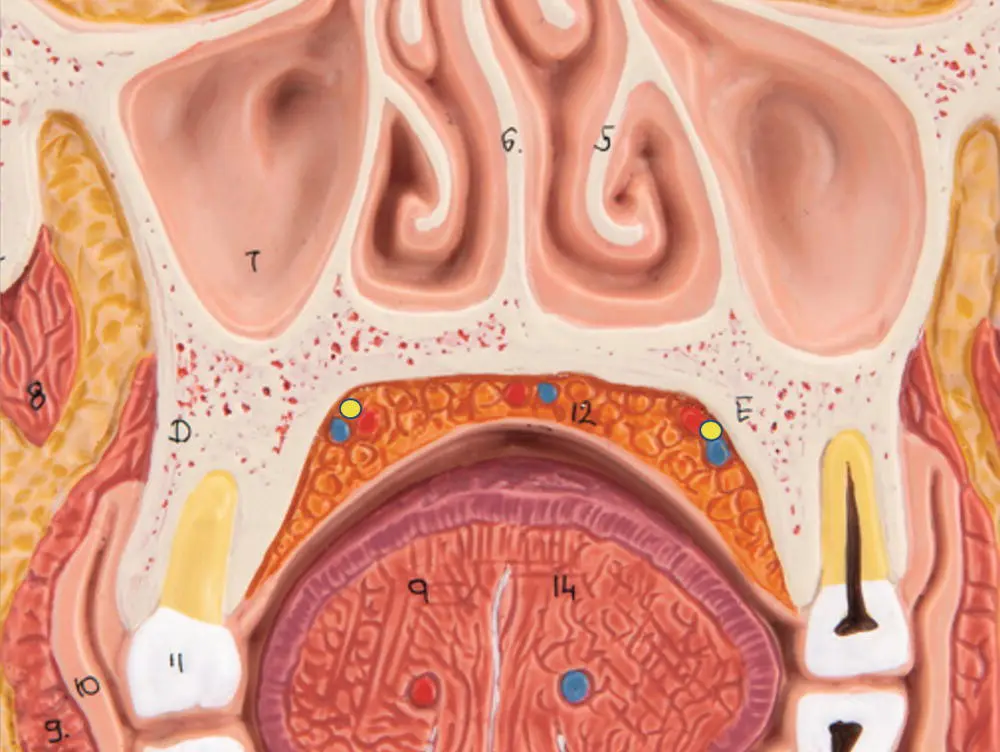

Upon exiting the greater palatine foramen located medial and slightly distal to the maxillary third molar, the greater palatine artery and nerve run anterior along the hard palate to the incisive foramen as described earlier. The greater palatine neurovascular bundle is typically located at the junction of the vertical and horizontal palatal walls of the palatal vault ( Figure 7.5).

Figure 7.5 Position of the greater palatine artery and nerve. The greater palatine neurovascular bundle is outlined in purple in the frontal section of the skull at the level of the premolars. Individuals with higher palatal vaults exhibit greater distances from the lingual gingival margin to the neurovascular bundle than lower palatal vaults.

When creating an incision in the region of the greater palatine artery a zone of safety should be maintained to avoid injury to the artery with potential resulting bleeding and soft tissue necrosis. This zone of safety will often depend on the anatomical variation of the individual patient. Although the greater palatine neurovascular bundle is typically located at the junction of the vertical and horizontal palatal walls, significant variations in palatal vault depth mean the neurovascular bundle could be as close as 7 mm from the lingual gingival margin at the first molar site in low palatal vault phenotypes to as much as 17 mm in high palatal vault phenotypes [28]. The harvest of connective tissue grafts and free gingival grafts is routinely performed in the maxillary posterior palatal tissues from the first molar site forward to the canine. In most dentate patients without significant periodontal disease it is possible to harvest connective tissue and free gingival grafts up to 8 mm in height without injury to the neurovascular bundle [29].